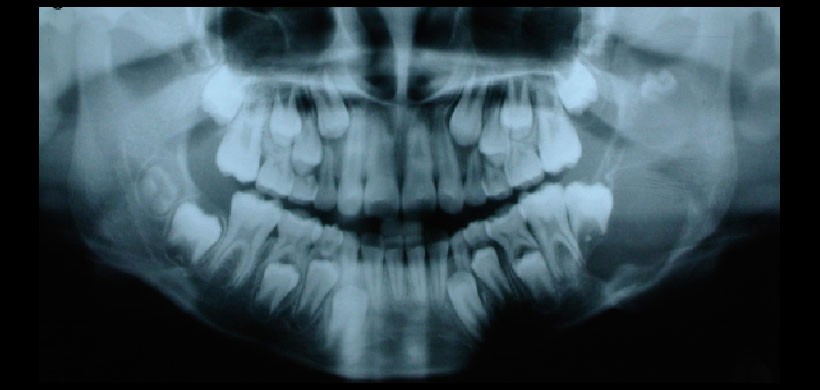

Fig 2.  Radiografía panorámica del caso anterior. Se visualiza una extensa lesión radiolúcida de contenido, comprometiendo el cuerpo y la rama mandibular izquierda y produce el desplazamiento del germen del tercer molar inferior